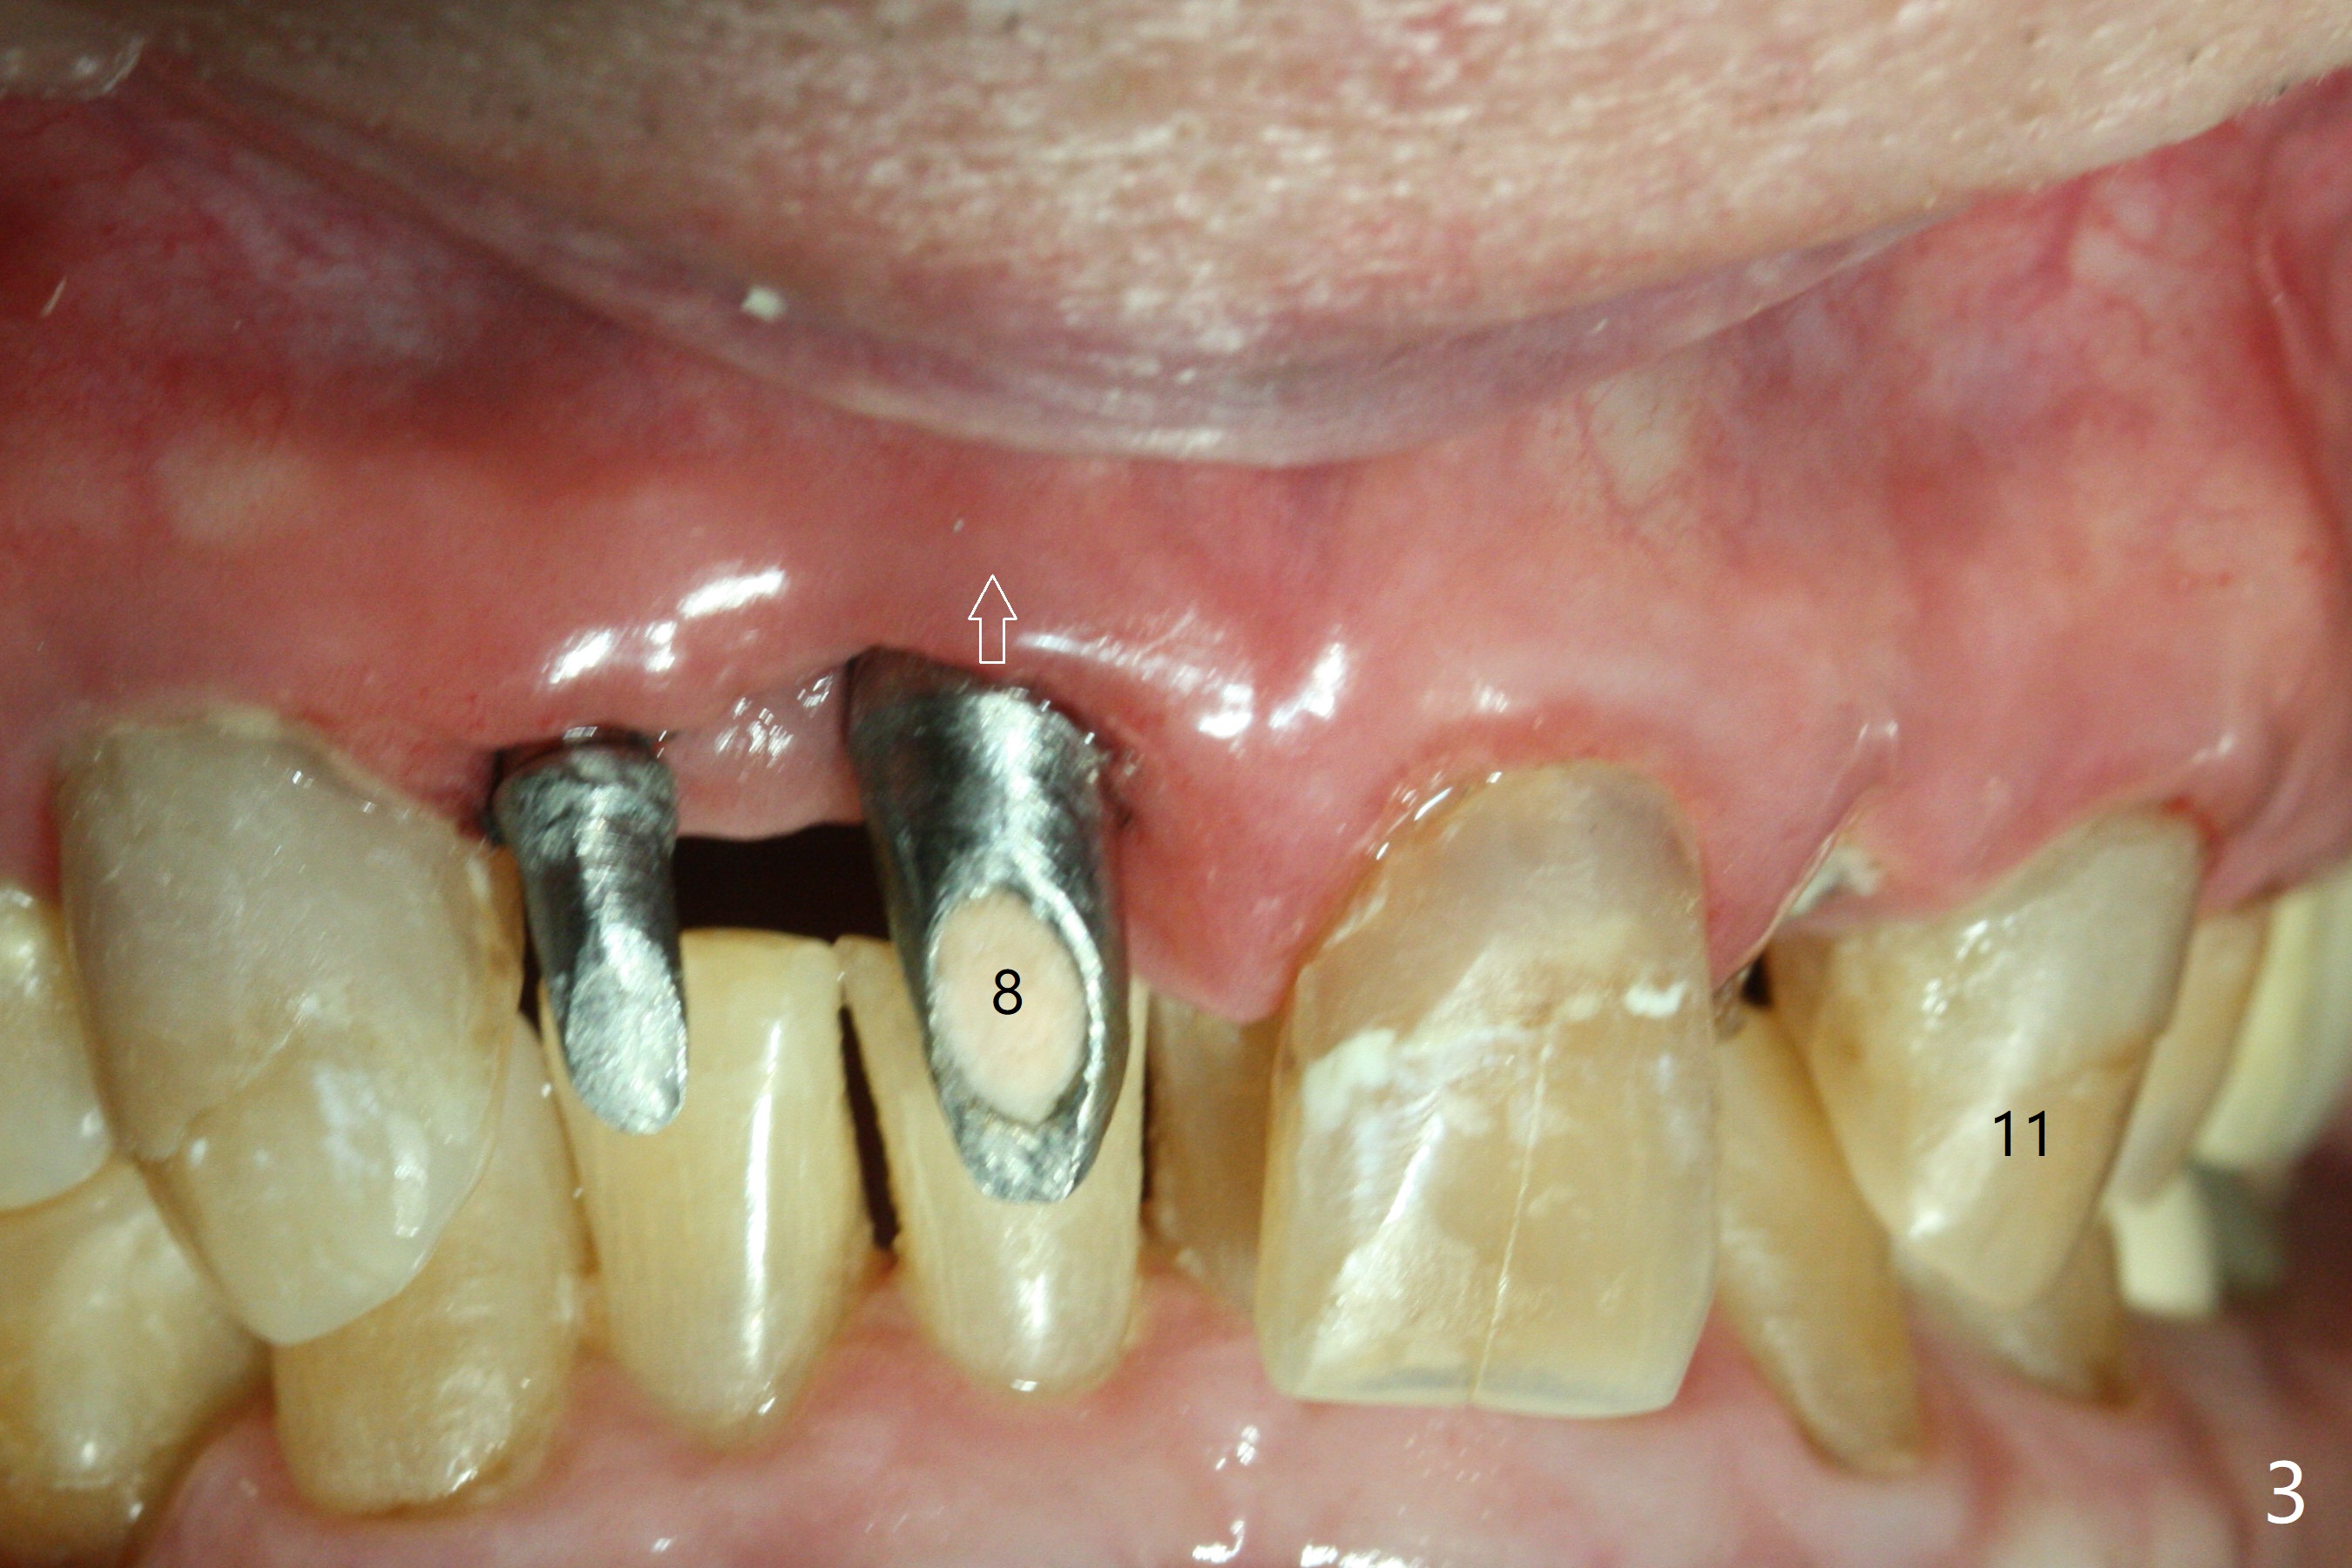

A 89-year-old man has poor dentition (Fig.1). After caries control (Fig.2), implants are placed at #7 and 8 (Fig.3). Because of the buccal plate fracture associated with extracted the ankylosed tooth #8, postop gingival recession occurs (Fig.3 arrow). To prevent the complication, socket shield will be performed if extraction of the tooth #10 turns out to be difficult. A 2.5 or 3x16 mm 1-piece or 3.5x13 mm/3.8x15 mm 2-piece implant will be attempted to be placed. Take preop photos to show #7 and 8 crowns and #10 residual root . Incision may be made to expose the labial crest to make sure that the the remaining labial portion of the root is caries free after extraction with sectioning.